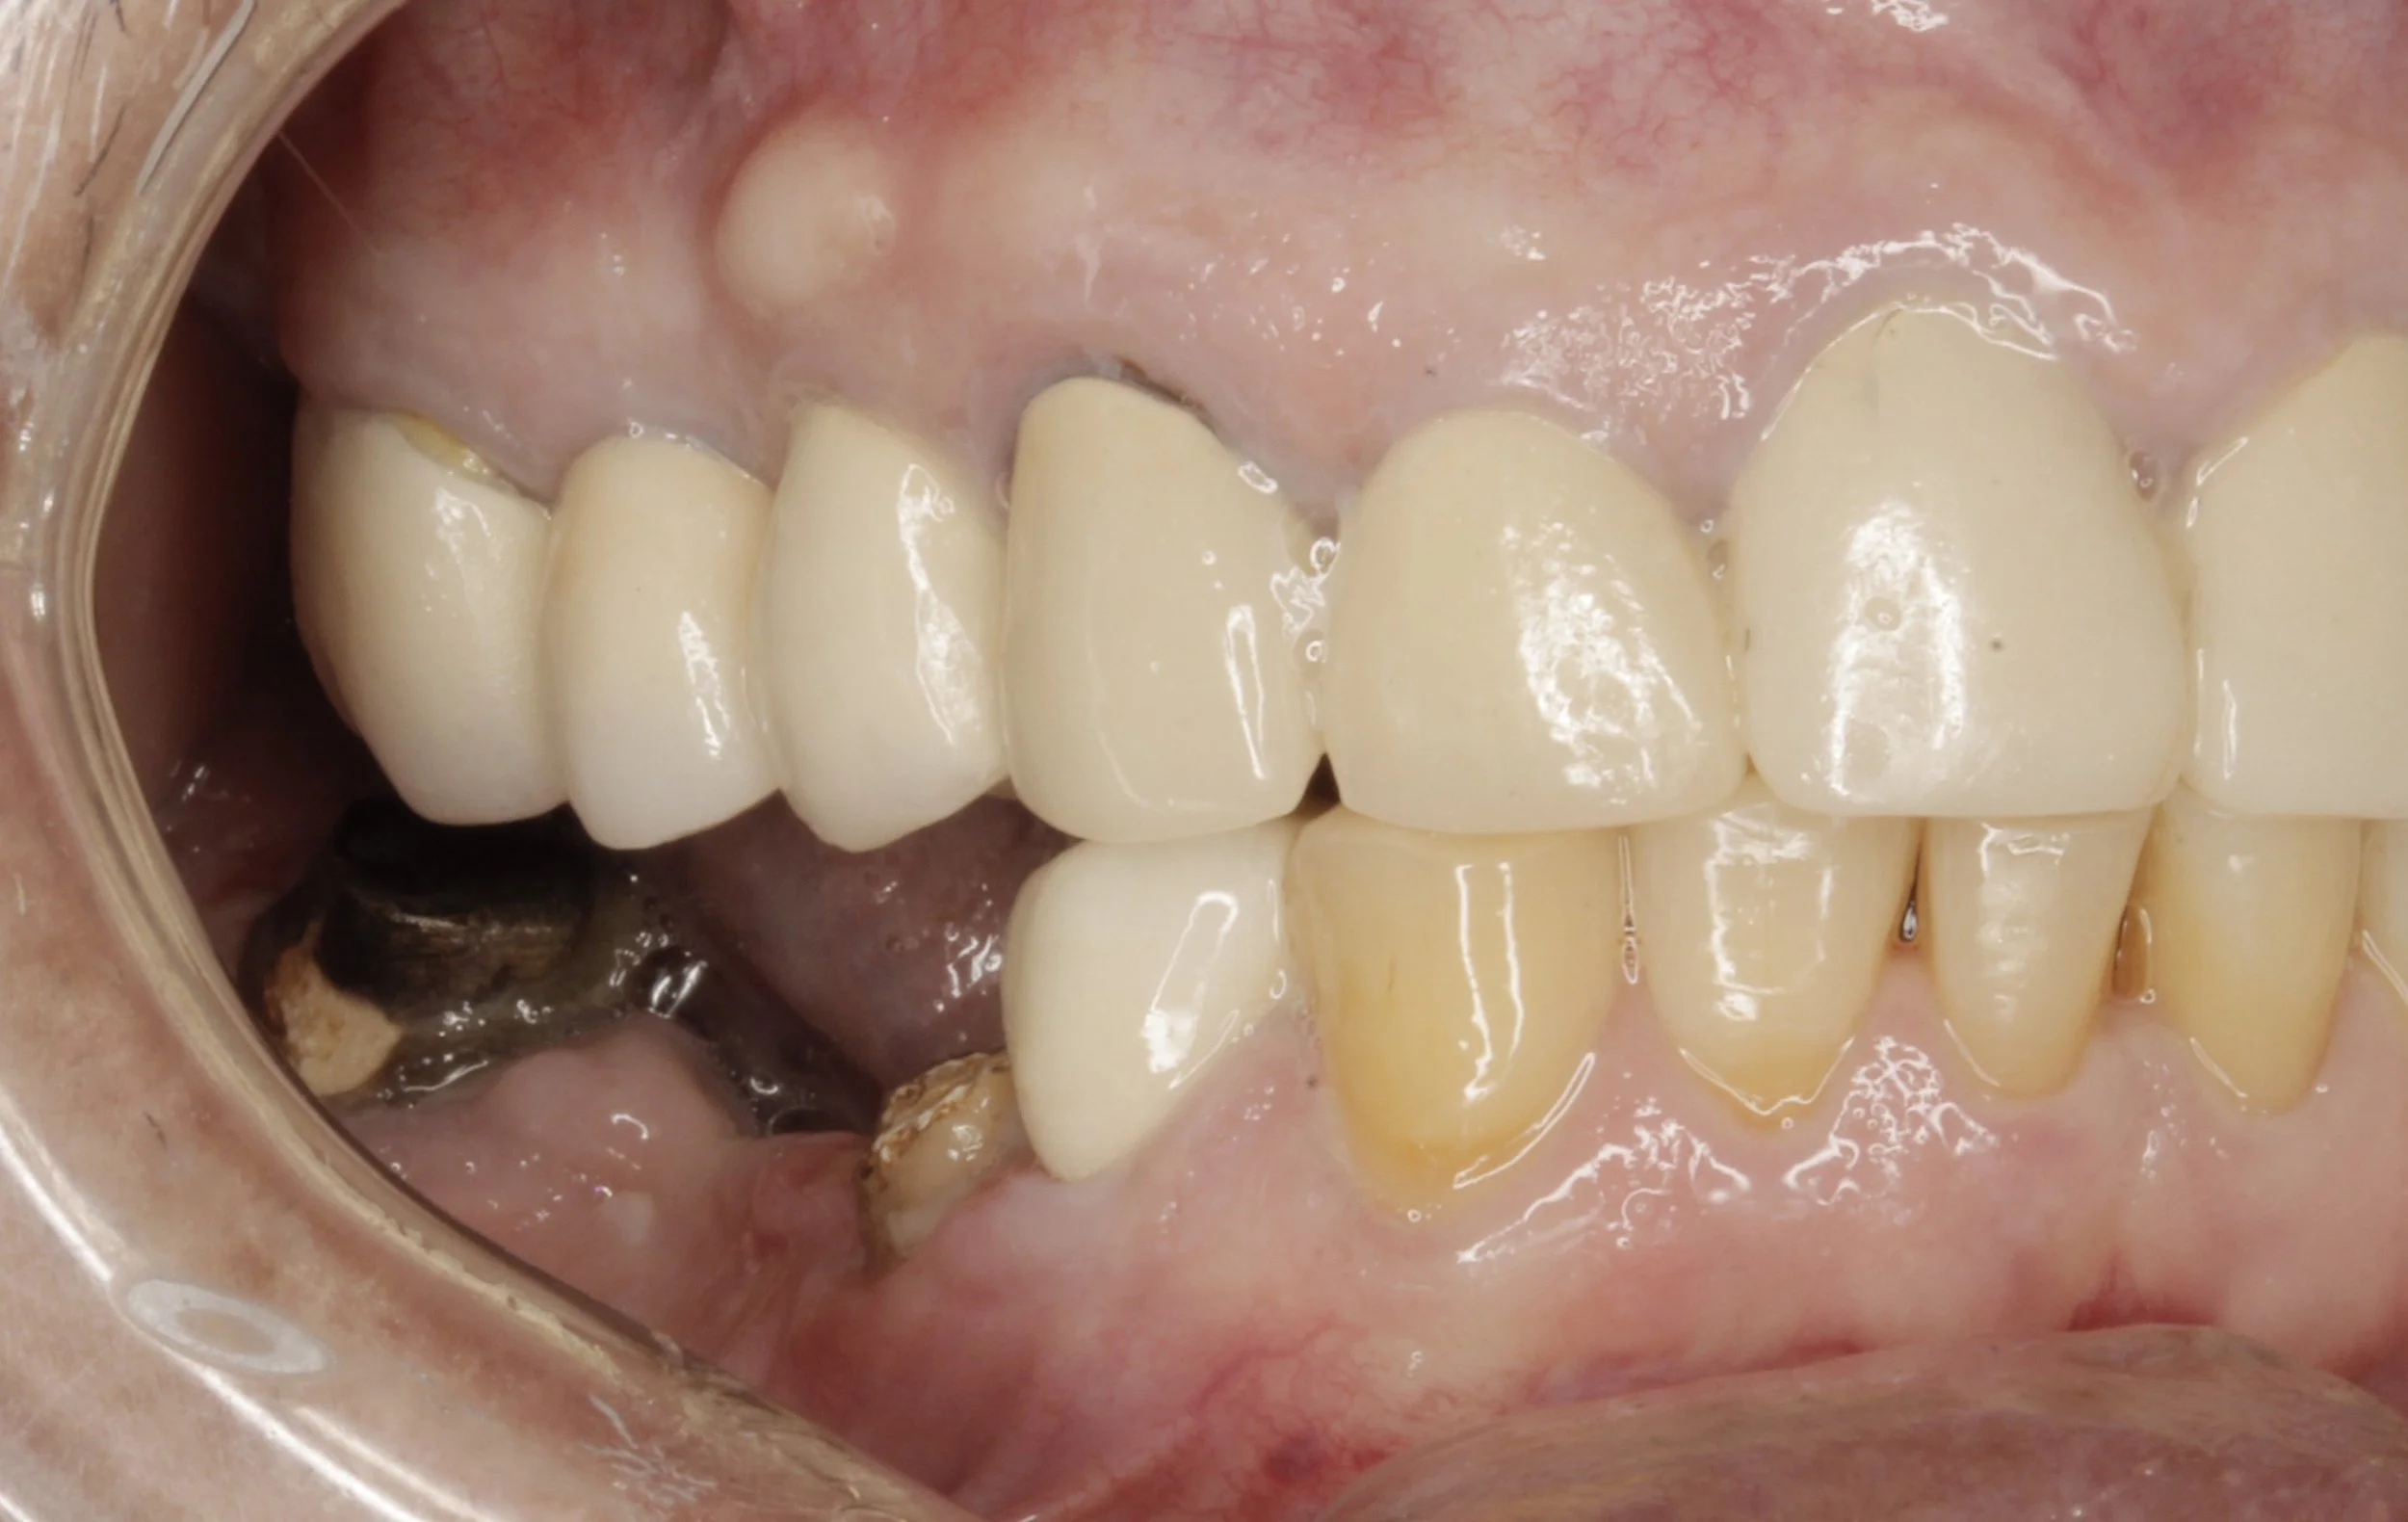

Antes

Fractura de puente fijo